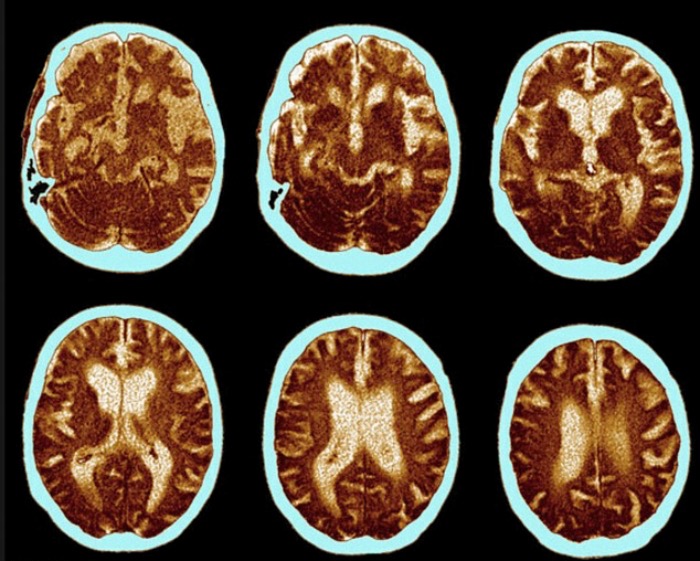

而杀死女性的“最大元凶”则是老年痴呆症—它同时也是男性的“二号杀手”,老年痴呆症每年令51000英国人死亡。

近日公布的官方数据显示,死于老年痴呆症和阿尔茨海默症的女性数量是死于乳腺癌女性的三倍。

死于老年痴呆症的女性比例由2013年的12.2%上升为2014年的13.4%。

业内普遍认为,这一数字上升的原因是医生对这种病有更深的认识,在记录病人死亡原因时有更大的意愿将此病列入,另外一个原因就是人类的寿命增加。

在2012年,老年痴呆症第一次超越心脏病成为英国女性的第一大死因。